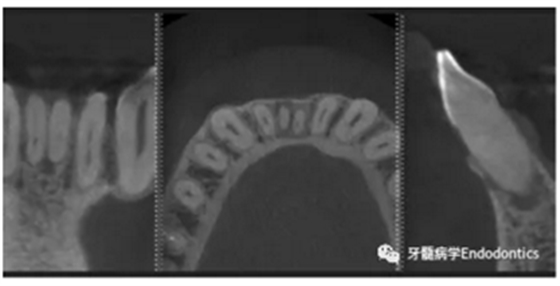

31、41叩痛明顯,牙冠變色(圖1)。溫度和牙髓電活力測(cè)試無反應(yīng)。兩張從不同角度拍攝的x線片顯示,相對(duì)于側(cè)切牙,雙側(cè)下中切牙都有嚴(yán)重的根管鈣化(圖2)。41有明顯根尖周暗影,31根尖周暗影不明顯。為進(jìn)一步證實(shí)31是否存在根尖周病變,同時(shí)精細(xì)觀察31、41的復(fù)雜結(jié)構(gòu),根據(jù)歐洲牙髓病學(xué)會(huì)CBCT應(yīng)用指南(2014),對(duì)患牙拍攝小視野、高分辨率CBCT。CBCT影像證實(shí)31、41均伴有根尖周炎和嚴(yán)重的根管鈣化(圖3)。距離根尖4mm可見根管影像。 由于患牙根管解剖結(jié)構(gòu)較為復(fù)雜,筆者決定使用特殊設(shè)計(jì)的微型鉆頭(直徑0.85mm)進(jìn)行“數(shù)字化導(dǎo)航牙髓治療”。 因此對(duì)下頜進(jìn)行口內(nèi)掃描(圖4)。用coDiagnostixTM軟件(Dental Wings Inc.,Montreal,Canada)將CBCT和口內(nèi)掃描的數(shù)據(jù)進(jìn)行處理,該軟件主要用于引導(dǎo)種植。通過該軟件對(duì)兩個(gè)掃描圖像進(jìn)行疊加后,虛擬鉆頭尖端沿牙長軸對(duì)準(zhǔn)根管下段可見部分(圖5)。三維檢查虛擬鉆的正確位置。

圖3.下頜前牙CBCT影像。